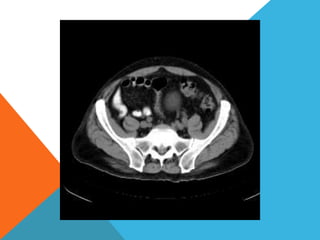

El paciente presentó síntomas de sangrado digestivo y pérdida de peso. Exámenes revelaron gastritis crónica asociada a H. pylori. Un tumor fue descubierto en una colonoscopia normal. La cirugía removió un tumor fibroide solitario, una rara neoplasia mesenquimal que usualmente crece lento y tiene bajo potencial de malignidad. El pronóstico después de la remoción quirúrgica es generalmente bueno.